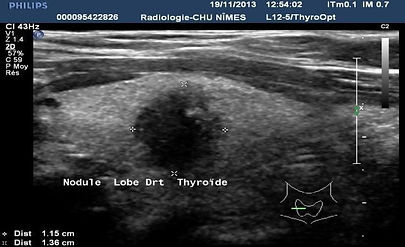

Cáncer papilar UE TIRADS 5

Microcalcificaciones

Rotura de cápsula